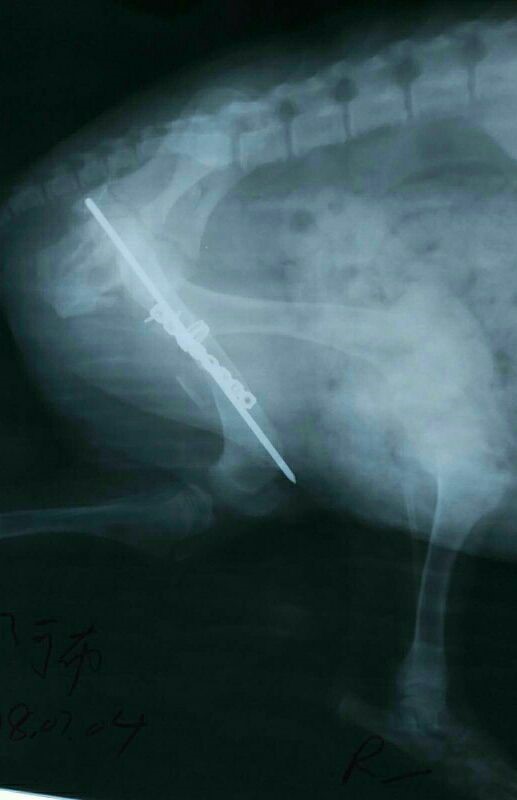

可憐的阿布(拉布拉多)因?yàn)橹魅说拇中拇笠獠凰ɡK子遛狗,造成阿布被車撞左后腿股骨骨折,后被主人遺棄在我院,救助小乖的愛心人士,樊女士知道阿布的事情后,同我院一起救助了阿布。目前阿布手術(shù)已做恢復(fù)良好一切正常。廣大養(yǎng)狗的主人們,遛狗一點(diǎn)要牽牽引繩,不要讓狗狗為你們的失誤或忘記買單,造成他們終身傷害。

術(shù)后: